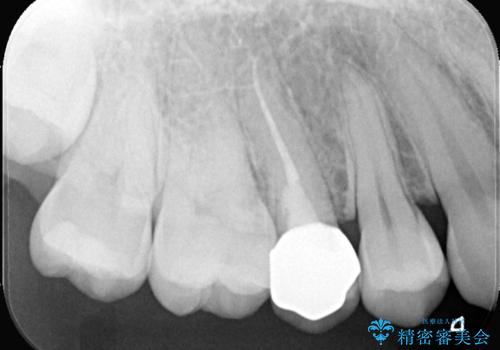

右上5番目の歯が根管治療途中となっており、前医院にて根管が狭く治療が難しいと言われてしまいセカンドオピニオンで当院にいらっしゃいました。

右上5番レントゲン写真上では根管が確認しずらく、根管の狭窄が予想されました。マイクロスコープを使用し、根尖部まで器具を到達させ十分根管洗浄を行うことができました。

・オールセラミッククラウン(スタンダード) 110,000円(税抜き)